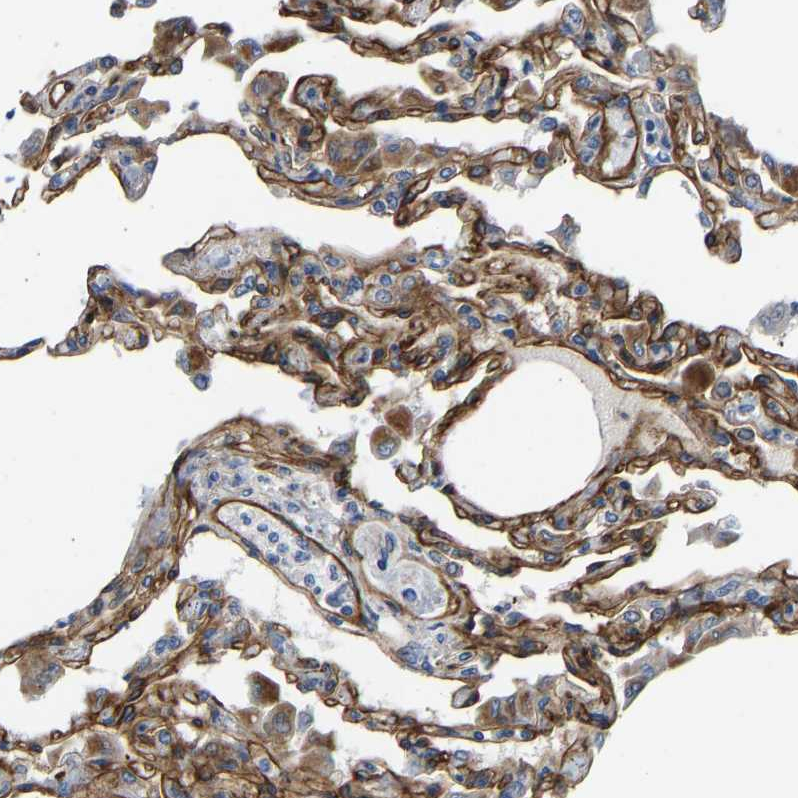

Immunohistochemical staining of human lung shows strong membranous positivity in pneumocytes.